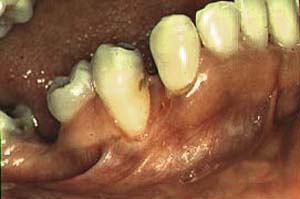

|

Secuestro óseo |